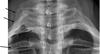

cervical rib

There are unfortunately several possibilities, from a slipped disc in the neck, to a first rib subluxation or a "cervical rib" that is affecting the group of nerves going down the arm.